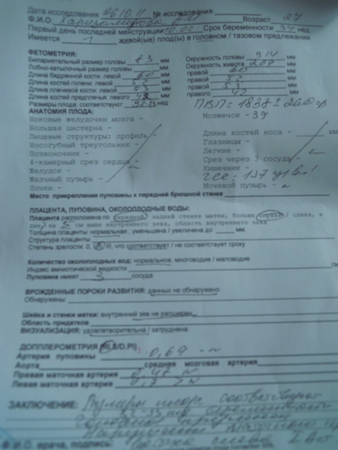

Результаты: УЗИ, КТГ, доплера, скринингаВчера с мужем и дочкой ездили на последнее плановое узи.Девочка наша стеснительная закрывалась ручками и прятала ножки,на ручке намотана пуповина(слава Богу ни на шее),щекастенькая такая и ножки не худенькие.Вес 1868гр(плюс минус 260гр),единственное что нас расстроило это нарушение маточного кровотока слева-врач сказала спать на левом боку и носить бандаж.На узи мне становилось несколько раз плохо,кидало в жар и кружилась голова,приходилось переворачиваться на бок-это врач сказала из-за того что матка давит.По узи нам 32-33 недели,так что родимся мы в конце ноября или в начале декабря.А вот и наша красотка